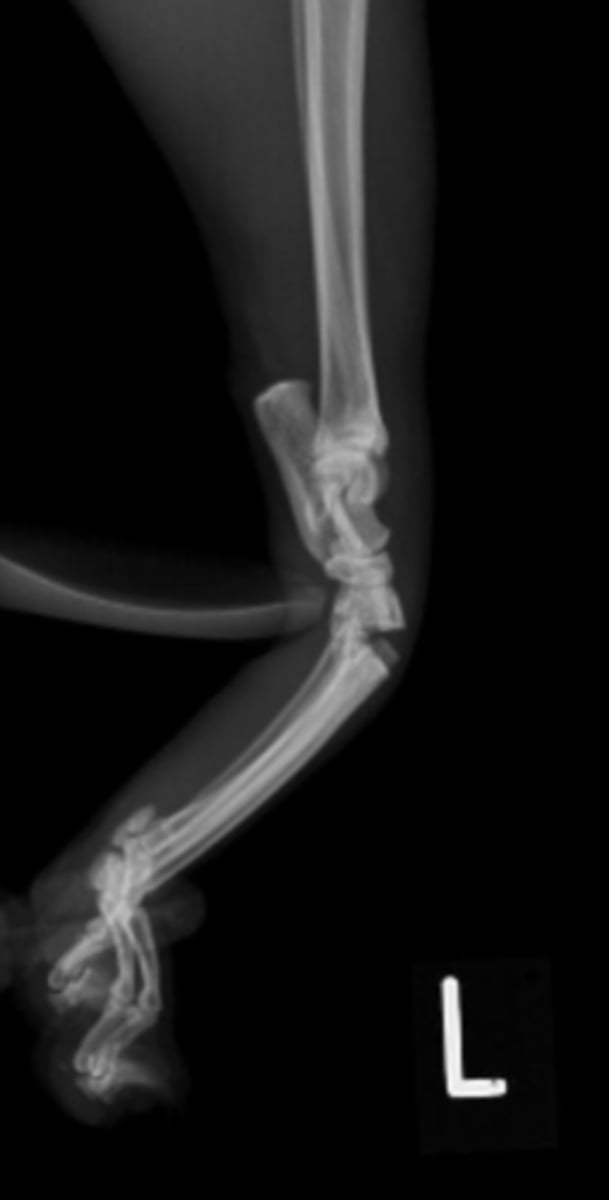

Radiopaque

white and light gray objects in the radiograph/ultrasound. bones and metal.

Radiolucent

black or dark gray objects in the radiograph/ultrasound. tissue, air, fluids.